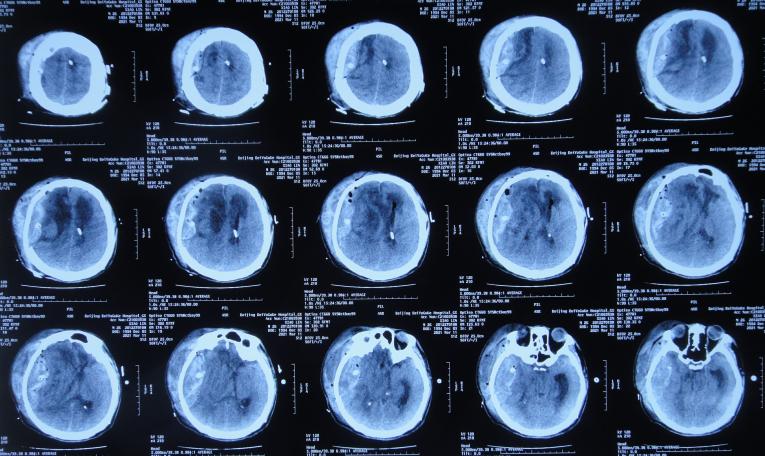

入院治疗22天即2021年1月18日,查头颅CT示脑膨出变基本正常( 图-13 );脑脊液细菌已被消灭。

图-13: 2021年1月18日头颅CT

入院治疗29天即2021年1月25日,查头颅CT示骨窗变塌陷( 图-14 )。

图-14: 2021年1月25日头颅CT

入院治疗31天即2021年1月27日,拔除了一侧脑室外引流管( 图-15 )。

图-15: 2021年1月27日头颅CT